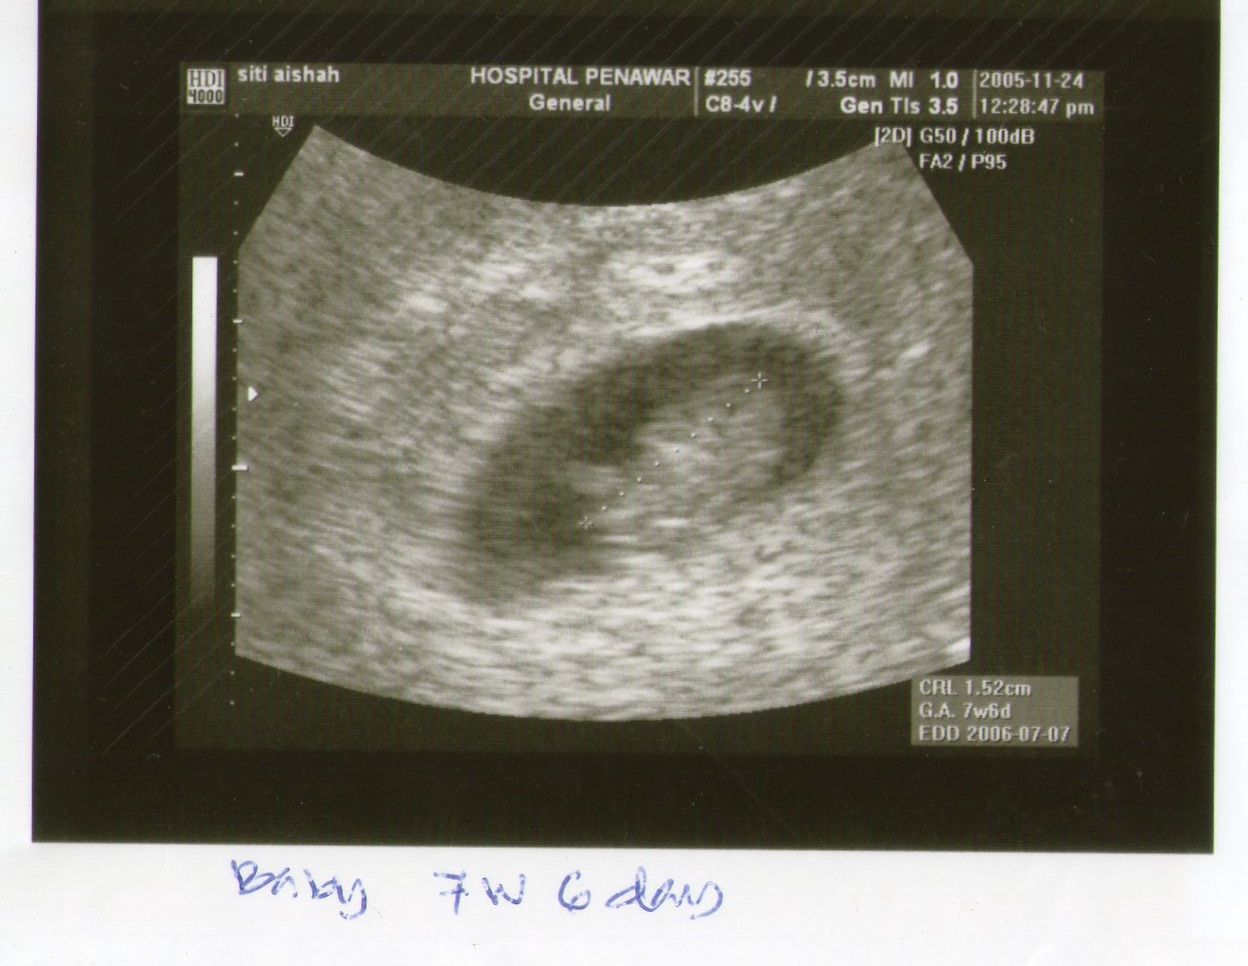

Sebelum aku kawin n selepas aku kawin aku mmg bekerja...org kata gile keje...pegi keja seblum jumpa matahari blk keja selepas tenggelam matahari...xde mende lain asek keje..keje..keje...mmg kaki kejelah..cari rezekikan...time anak dara oklah xde yg menunggu..tp bila dah kawin sblum laki aku kuo keja aku dah kuo dulu..laki aku dah blk aku pon belum balik.... smpailah aku peknen...sekali keguguran doktor kata aku strees pasal keja...kali ke 2 bila kompom doktor suh aku rehat..dia kata rahim aku x kuat...so aku pon bertukar arah dr kaki keja jd surirmhtangga..time tu mmg boring abes..mende nak buat kat rmh ekss..x reti aku nak duk diam...aku pon apply keja lain...peknen2 pun bole mintak keja ke..hehehehe...kata org rezeki anakkan..walaupun majikan ni tau aku peknen tp still nak amek aku keja..mungkin dia tau sbb aku kaki keja...hehhehe...dgn keizinan laki aku aku pon mula keja semula....